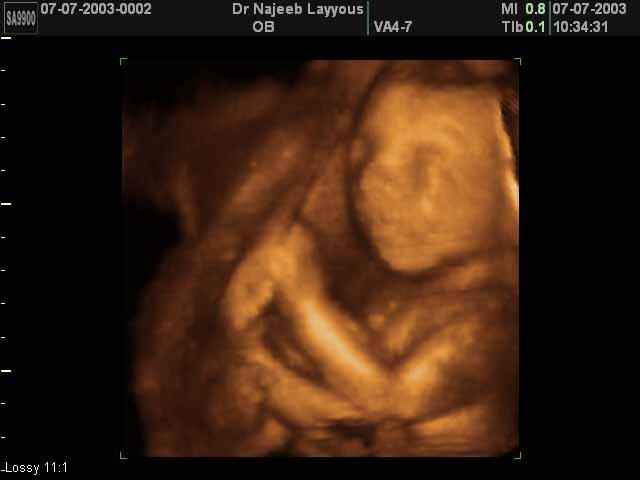

- 3D Fetal Profile Ultrasound Scan Photos

3D Fetal Profile Ultrasound Scan Photos | Dr N Layyous